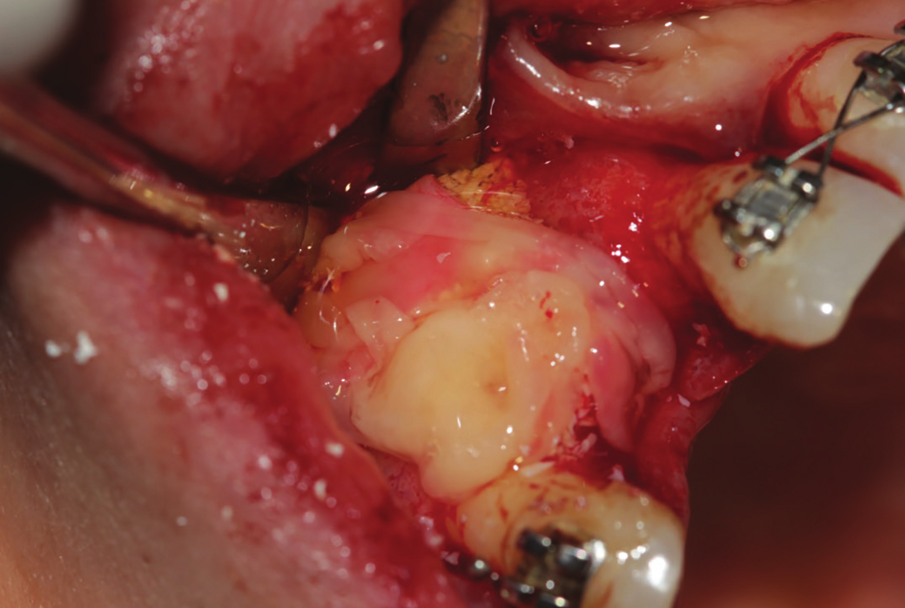

Figure 22: Inter operative view after reflection of mucoperiosteal flap, showing the extended amount of bone loss with intralesional secretion bulging outside the bone cavity.

Figure 23: Enucleation of the 1.5 cm lesion followed by extraction of endodontically perforated tooth no 7.

A 38 years-old female patient came to our clinic with swelling upper anterior area, she was medically fit with no health problems. The patient underwent an orthodontic treatment for 2 years and was about to remove it and place retainer. Intraoral examination showed swelling apical area of tooth no 7. The periapical x-ray and CAT view revealed a lateral perforation on the same mentioned tooth with a well circumscribed radiolucency in apical area (Fig.20, 21). Pain on percussion and slight mobility were noted. A surgical enucleation and extraction of tooth no 7 were conducted (Fig.22, 23, 24). 3 months postoperative CAT view shows an advanced horizontal bone loss with no recurrence of lesion in the area (Fig. 26), clinically after reflection of mucoperiosteal flap, the situation confirmed the CAT image (Fig.25) , the case was planned for PRF -associated bovine bone technique replacing the aggressive autologous bone graft procedure. After collection of PRF from patient blood culture, a first layer of L-PRF covering the bovine bone associated PRF complex (sticky bone) was done (Fig.27). The second layer of L-PRF came to cover the cross-linked collagen membrane (Fig. 28).